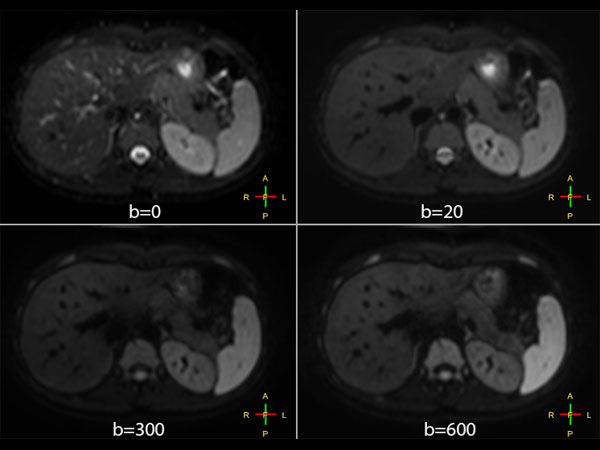

Liver imaging with MultiVane XD